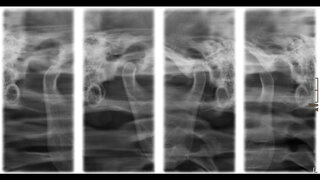

Medizinischer Meilenstein in der MKG-ChirurgieKiefergelenk-Endoprothese behebt temporomandibuläre Ankylose In Kassel wurde eine patientenspezifische Kiefergelenk-Endoprothese implantiert. Der hochspezialisierte Eingriff ermöglicht einer 55-Jährigen nach jahrelangem Leidensweg wieder eine nahezu normale Mundöffnung. 19.01.2026 ZahnmedizinChirurgie